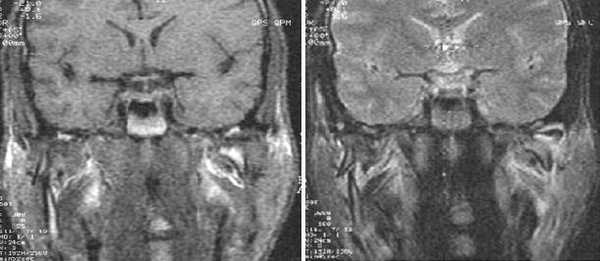

Каждое выполняемое исследование необходимо делать в 2-х положениях - с закрытым и открытым ртом.

Косо-сагиттальная проекция с закрытым ртом. Нормальный ВНЧС.

Суставной диск не дислоцирован, задняя его часть находится на 12 часах циферблата мыщелка.

Нормальная мобильность диска

Позиция с открытым ртом. Мыщелок сместился вентрально, на уровень суставной ямки. При этом суставной диск сохранил нормальное положение интерпозиции, не давая костным структурам напрямую контактировать друг с другом.